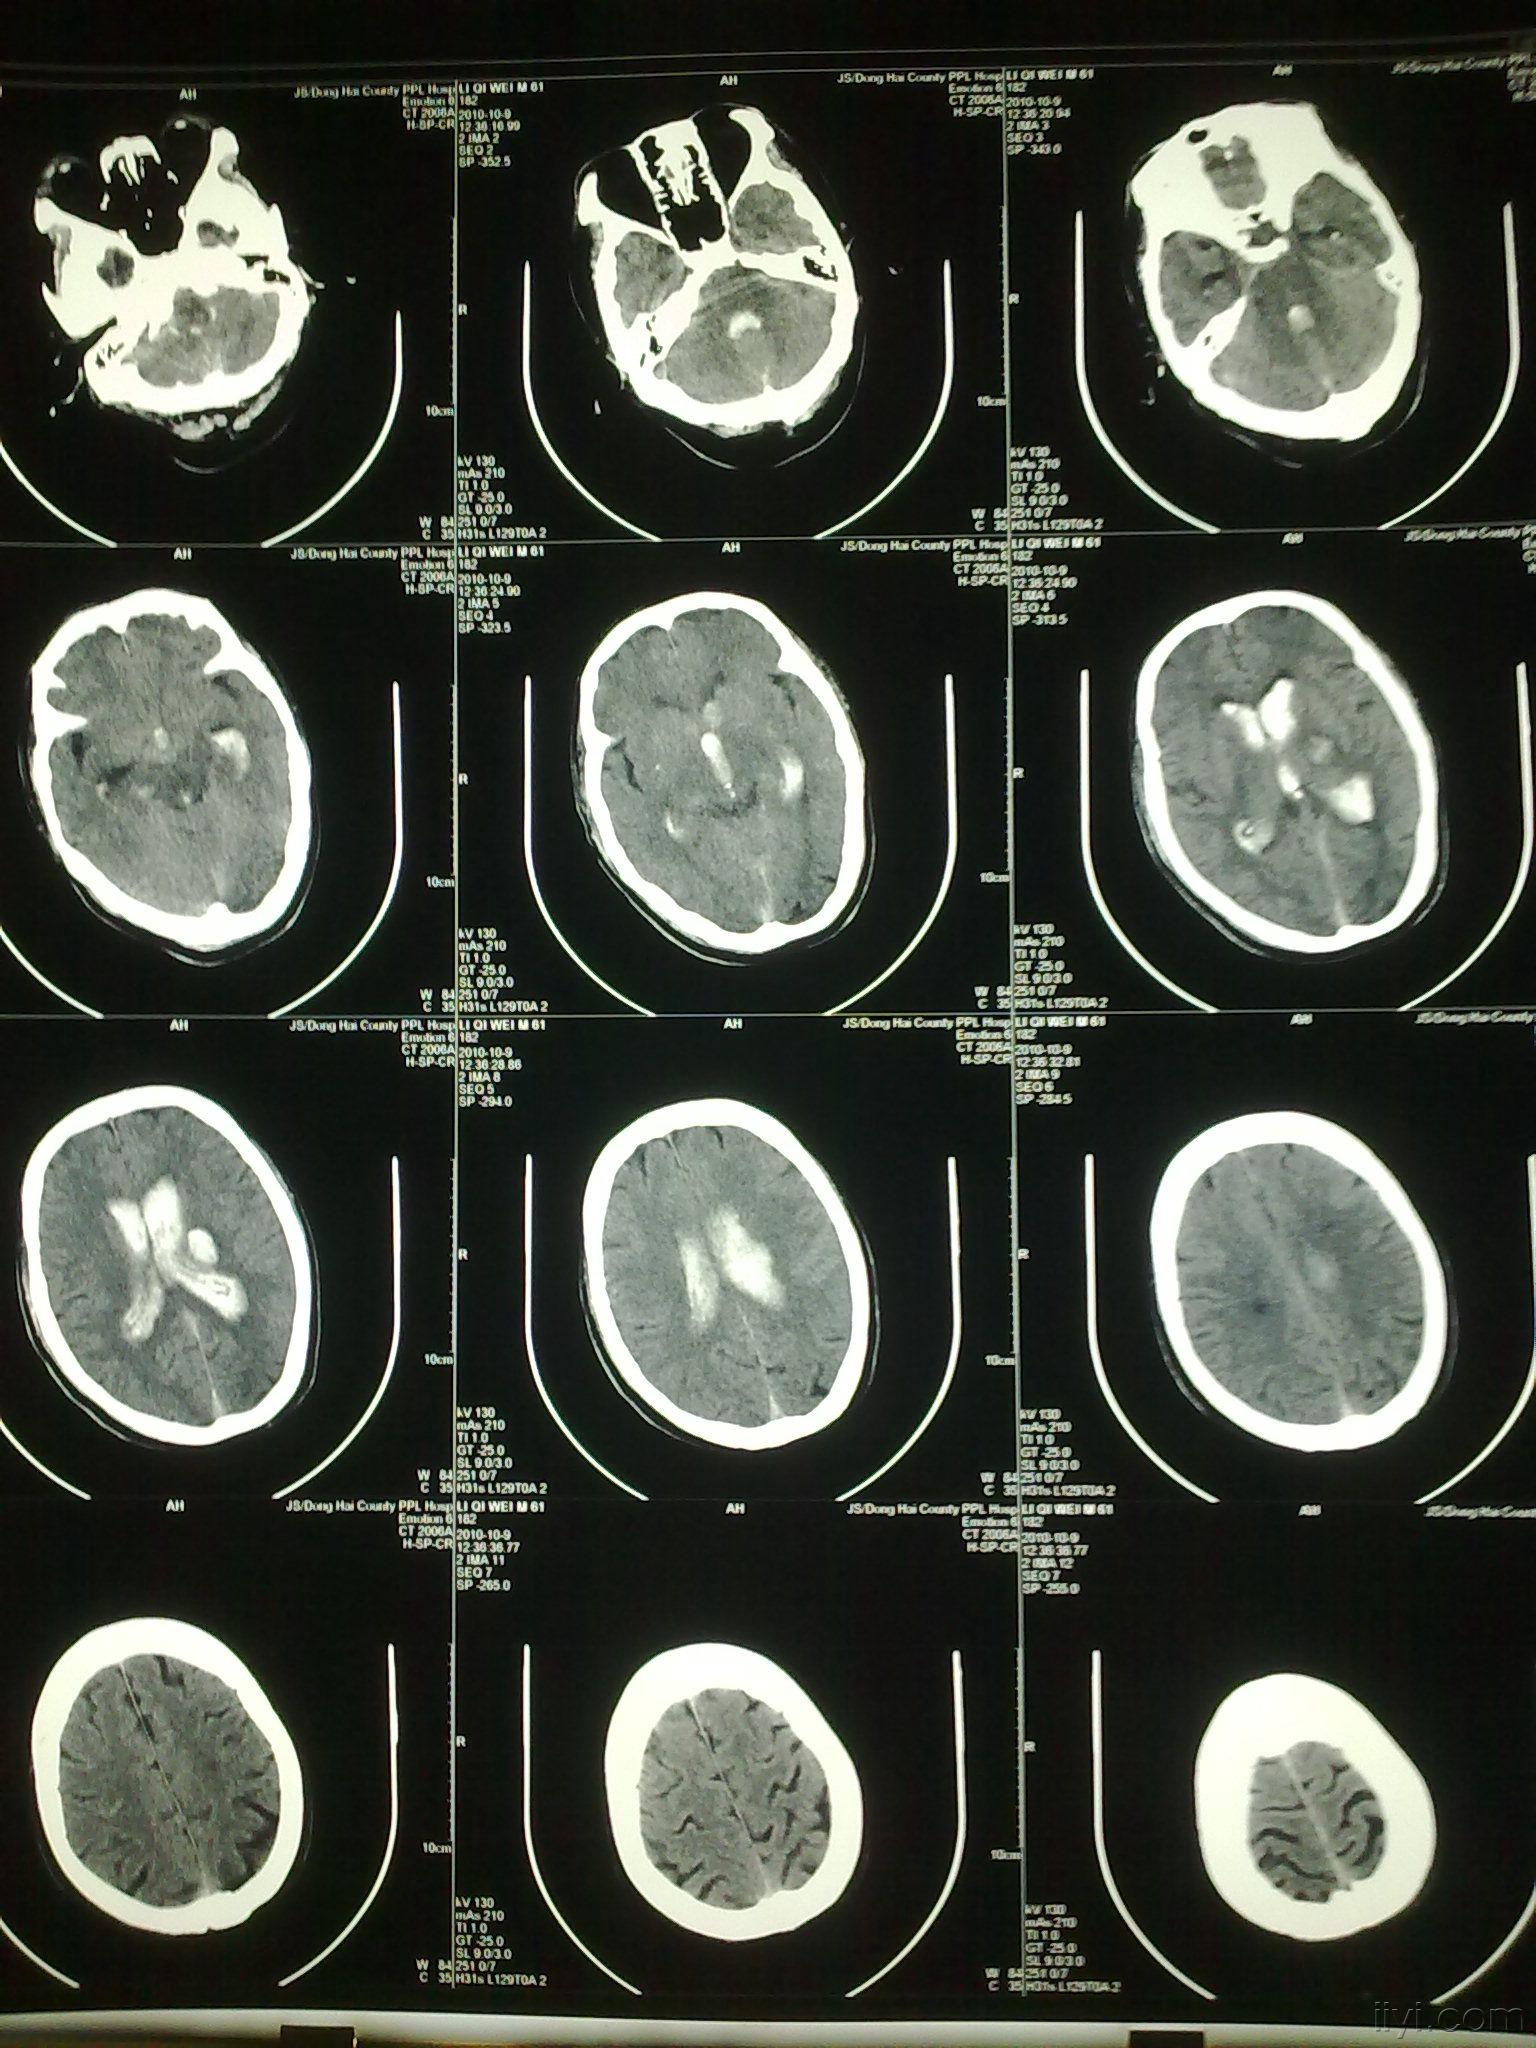

一例比较看似简单而又复杂的脑室铸型 - 神经外科专业讨论版 - 爱爱医

图片尺寸1536x2048